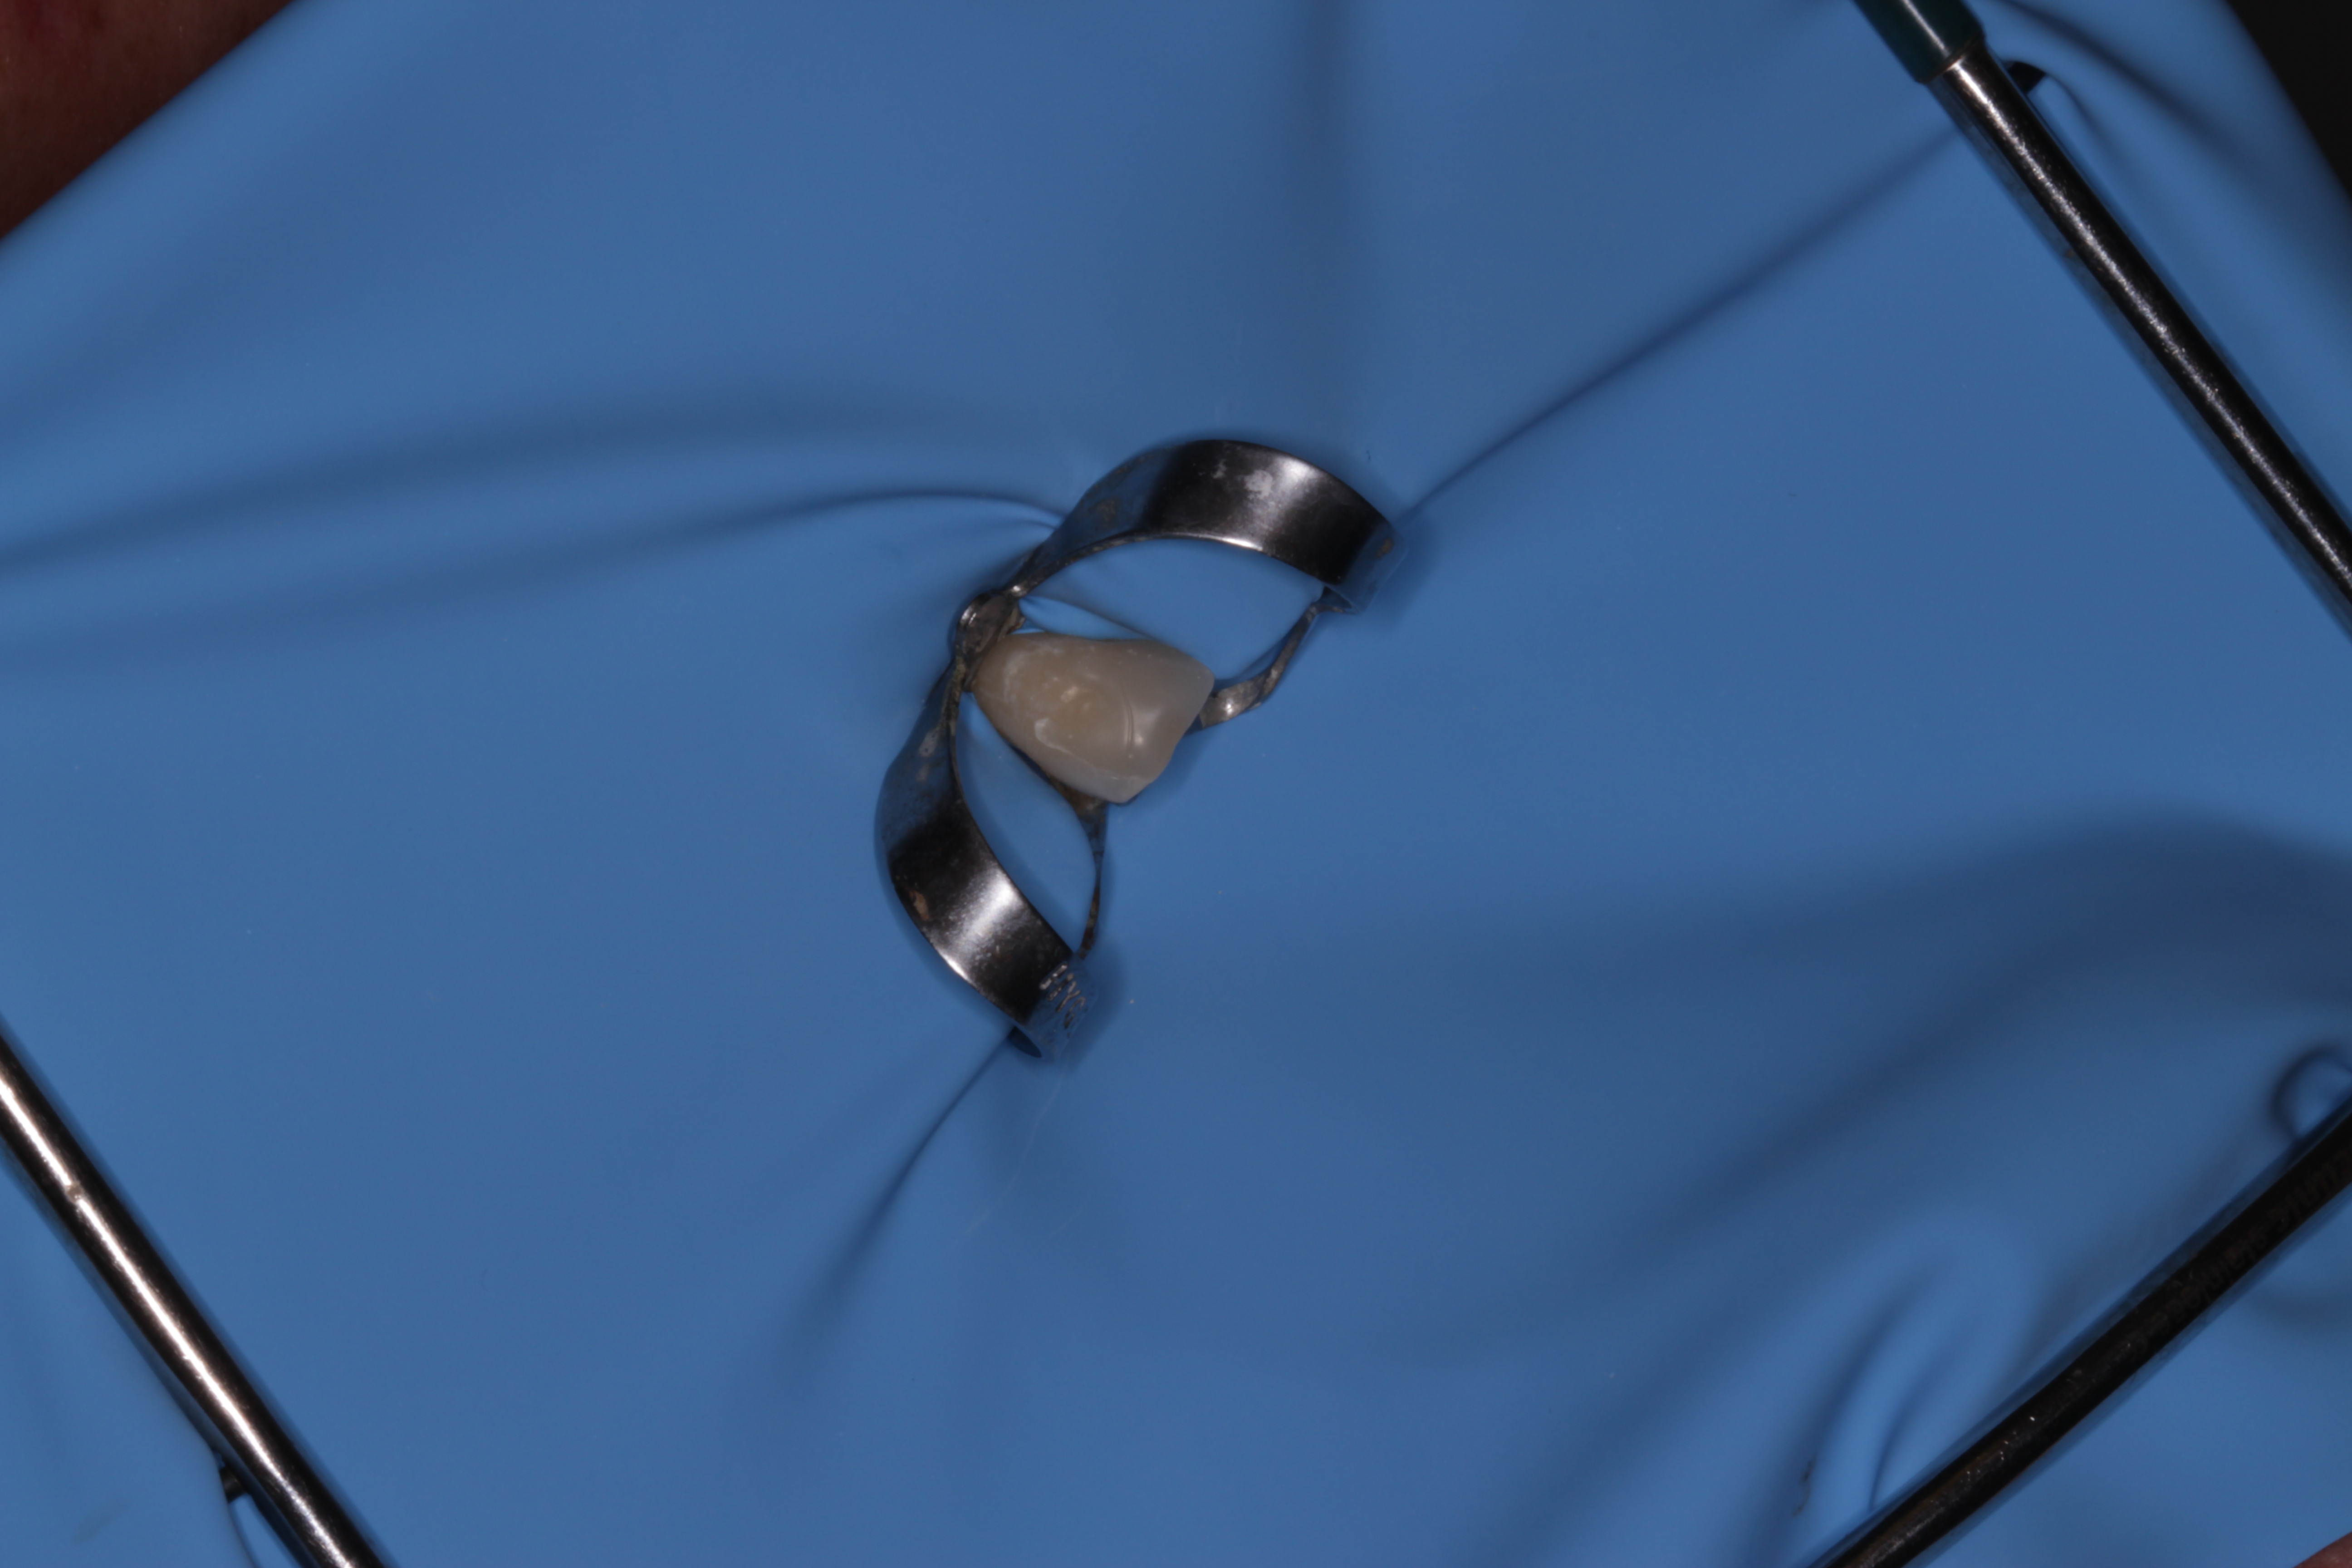

- Tratamiento

- Prótesis parcial acrílica

- Técnica BOPT